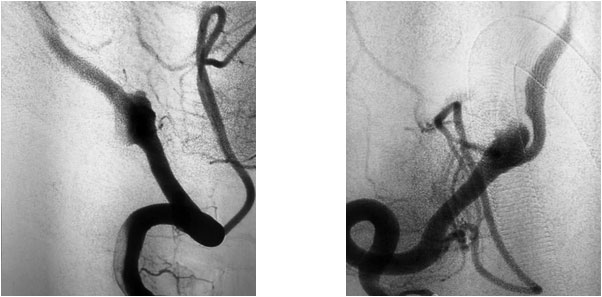

患者為65歲男性,20天前無明顯誘因突然出現(xiàn)四肢無力,呈漸進(jìn)性加重,以下肢為甚,伴頭暈、頭痛,呈一過性,在當(dāng)?shù)蒯t(yī)院急查頭顱CT示:右側(cè)椎動(dòng)脈V4段動(dòng)脈瘤。當(dāng)時(shí)癥狀自行緩解,未做處理。后患者自感癥狀間斷發(fā)生,為求進(jìn)一步治療,遂轉(zhuǎn)至上海藍(lán)十字腦科醫(yī)院。

患者既往有“高血壓”病史8年,“糖尿病”病史1年余。頭顱增強(qiáng)CTA示:右側(cè)椎動(dòng)脈V4段動(dòng)脈瘤,直徑7.5毫米,右側(cè)頸內(nèi)動(dòng)脈C4-6段多發(fā)鈣化斑塊形成,伴相應(yīng)管腔輕度狹窄,左側(cè)頸內(nèi)動(dòng)脈C5-6段微鈣化斑塊形成,左側(cè)椎動(dòng)脈偏細(xì)。

張琪博士指出,患者動(dòng)脈瘤雖未破裂但已壓迫大腦周圍神經(jīng),導(dǎo)致頭暈、頭痛及四肢無力等神經(jīng)系統(tǒng)癥狀和體征,手術(shù)指征明顯。

在充分準(zhǔn)備后,張琪博士在劉春醫(yī)生、周林華醫(yī)生協(xié)助下為患者進(jìn)行了支架輔助動(dòng)脈瘤栓塞手術(shù)。填入彈簧圈后,再置入支架,完全釋放后,造影顯示動(dòng)脈瘤無顯影,支架覆蓋良好,載瘤動(dòng)脈通暢,撤出微導(dǎo)管輸送系統(tǒng),復(fù)查雙側(cè)椎動(dòng)脈造影顯示遠(yuǎn)端血流通暢。

▲ 術(shù)前影像